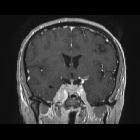

cavernous sinus mass

sinus mass • Meckel cave meningioma - Ganzer Fall bei Radiopaedia

sinus mass • Trigeminal schwannoma - Ganzer Fall bei Radiopaedia

sinus mass • Intracranial aneurysm - Ganzer Fall bei Radiopaedia

sinus mass • Chondrosarcoma - sphenoid wing - Ganzer Fall bei Radiopaedia

sinus mass • Tolosa-Hunt syndrome - Ganzer Fall bei Radiopaedia

sinus mass • Neurolymphomatosis - Ganzer Fall bei Radiopaedia

sinus hemangioma • Cavernous sinus hemangioma (huge) - Ganzer Fall bei Radiopaedia

• Cavernous sinus meningioma - Ganzer Fall bei Radiopaedia

A cavernous sinus mass has a wide differential including: